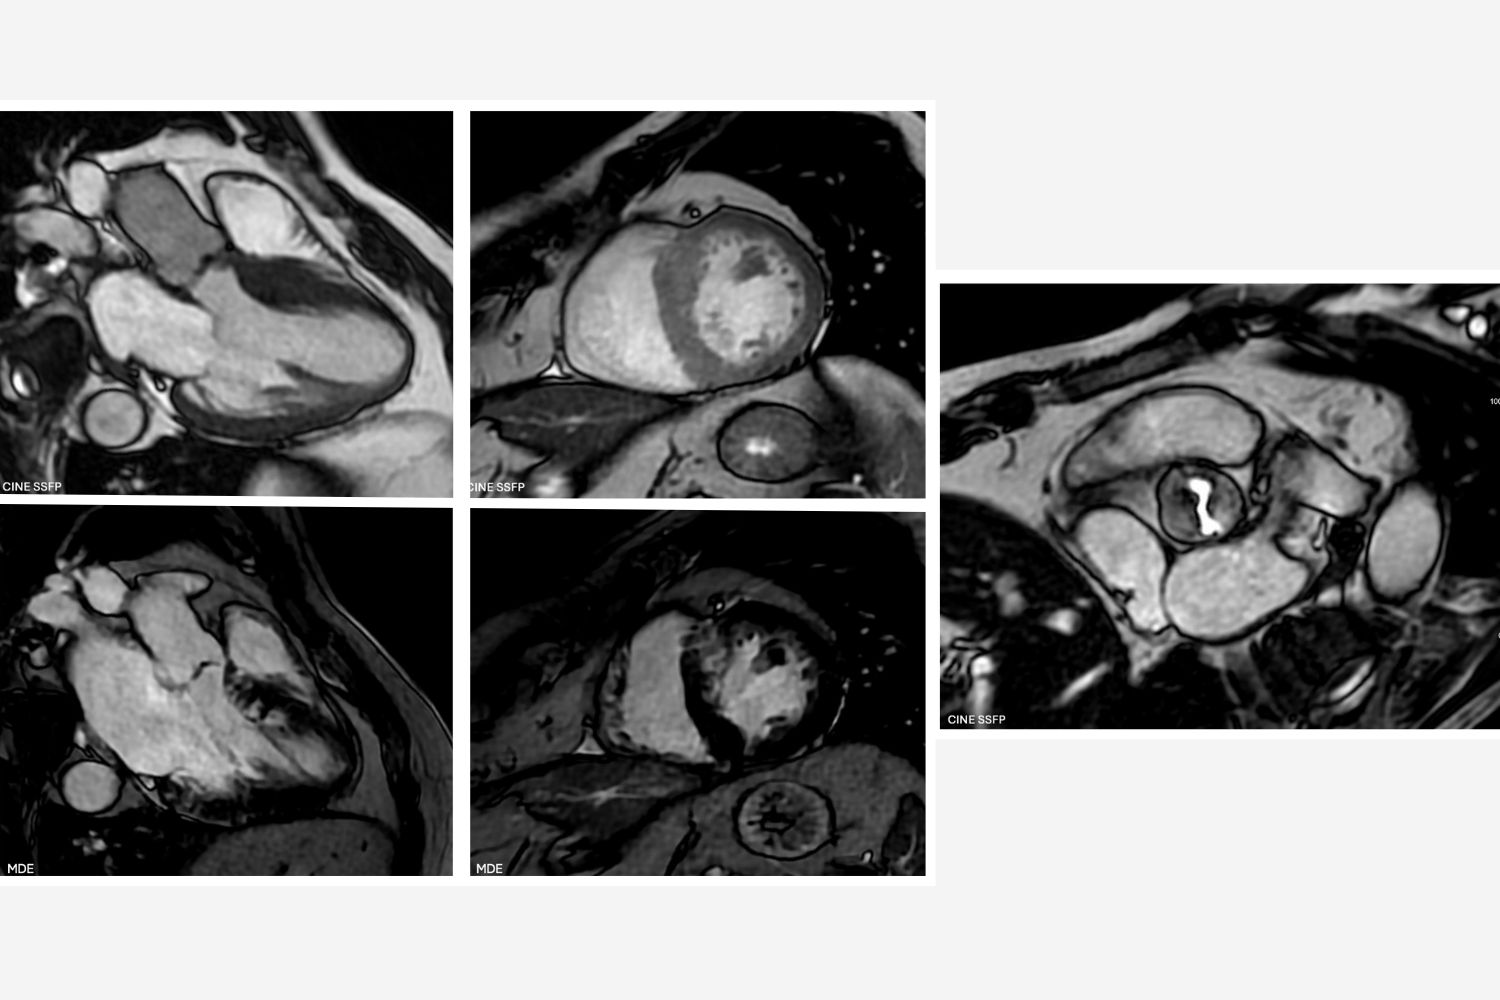

Image of the Week -12 March 2025

Image of the week